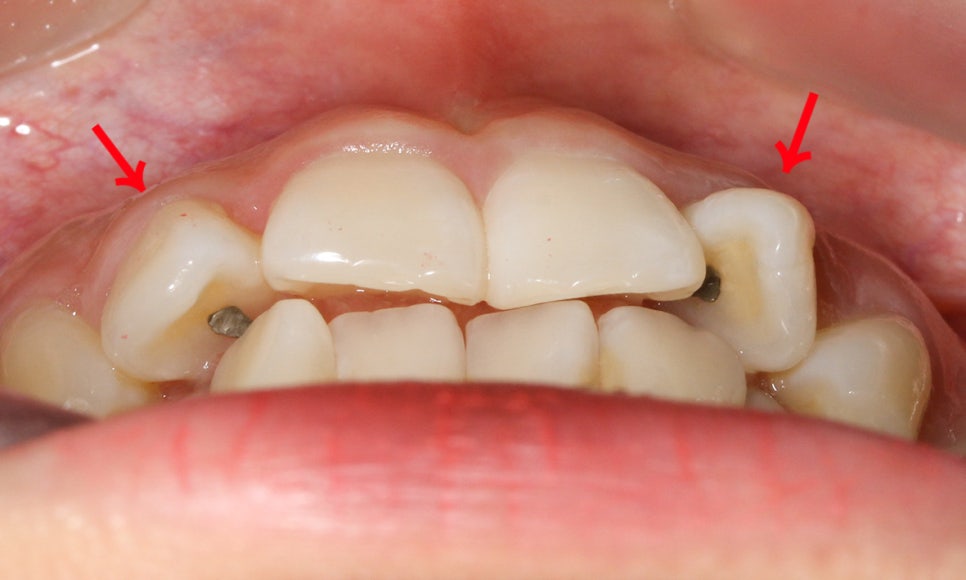

10~40번대 치아들의 교합 평면을 보시면

구치부쪽 교합은 비교적 틀어지지 않은 모습으로

전치부의 앞니틀어짐과 crowding을 해결한다면

성공적인 교정 결과를 기대해 볼 수 있는데요,

반대쪽 교합평면 또한 하악의

curve of spee가 깊지 않은 것으로 보아

전체적으로 치아의 삐뚤어짐을 중심으로

교정 계획을 수립해야 할 것으로 보입니다.